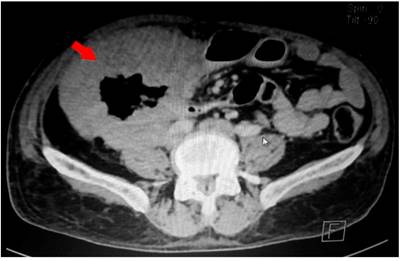

La ecografía abdominal reportó que a nivel del flanco derecho se observa un asa intestinal de paredes engrosadas irregulares de aspecto tumoral de 79 x 78 mm con ecografía Doppler e incremento de la vascularización. En la tomografía axial computarizada (TAC) de abdomen y pelvis se observa un engrosamiento difuso de las paredes del ángulo hepático hasta el colon ascendente y ciego con alteración de la grasa pericecal, y cambios inflamatorios en el íleon terminal, por lo que se debe descartar lesión primaria en el ciego (Figuras 1 y 2). Se realizó un estudio endoscópico digestivo alto en el que se observó una pangastropatía atrófica; la colonoscopia reveló que en todo el colon se observó alteración del patrón vascular, eritema, granular, edematosa, friable, a nivel del ángulo hepático una estenosis de aspecto maligno que impide el paso del equipo con un reporte colonoscópico de pancolitis activa con un puntaje de Mayo 2 para colitis ulcerativa. Se tomó una biopsia de la estenosis y de todos los segmentos y se reportó infiltrado inflamatorio grave de linfocitos y células plasmáticas, neutrófilos en la lámina propia, neutrófilos en el epitelio, daño epitelial, daño en las criptas de la superficie, criptitis, absceso críptico agregados linfoides, ulceración superficial y profunda, y pérdida de algunas células caliciformes sugestivos de colitis ulcerativa; y en el resto de los segmentos no se observaron granulomas sugestivos de colitis ulcerativa.